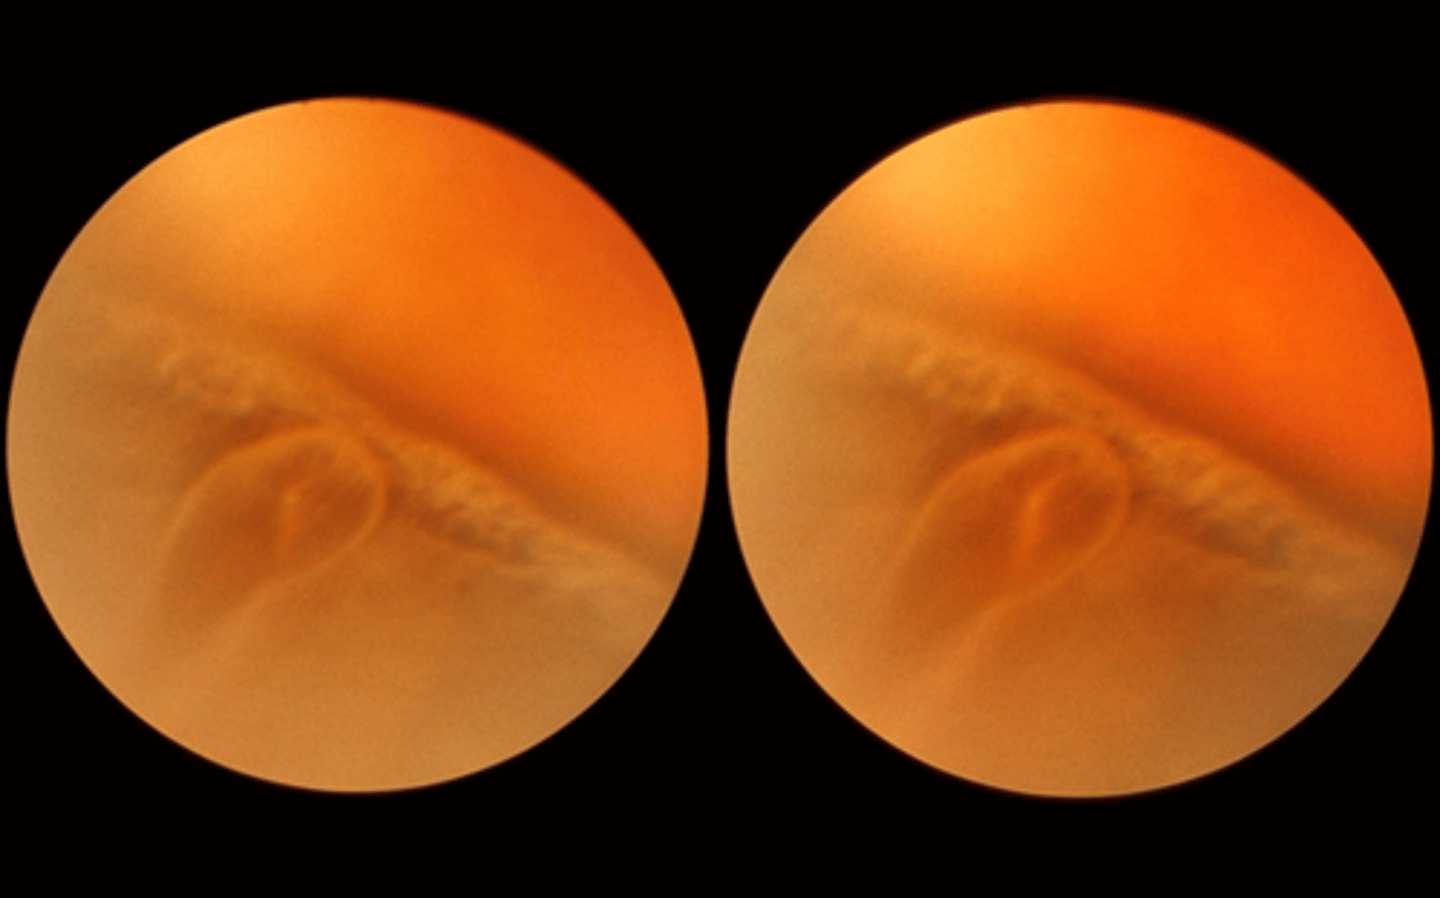

White without pressure : aetiology

Asymptomatic

•White-grey appearance of the equator and/or peripheral retina

•Well demarcated scalloped borders

•Seen without scleral indentation (CF: white with pressure)

•Occurs in about 30% of all patients

• More common in patients with dark skin

•Usually bilateral

•Benign

White without pressure: differential diagnosis

-Subclinical retinal detachment

• Retinoschisis